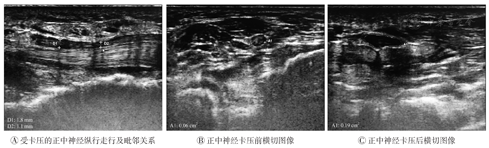

超声检查结果表明,在高频超声下,CTS组与对照组手腕的正中神经均可连续全程探及,并可追踪至肘部(图1A);正中神经在腕管入口、中部及出口处横切面均呈圆形或呈扁椭圆形,内有强回声散点状分布,周围呈高回声包绕(图1B)。CTS组的患腕腕管处正中神经肿胀增粗,内部结构分布不清,高回声减低(图2)。